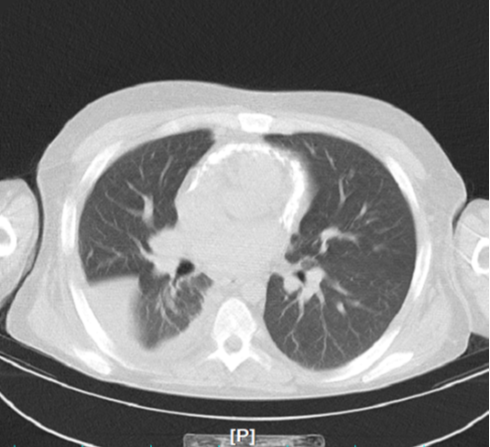

with mild hepatomegaly noted on physical examination. Besides hypotension, the patient did not complain of any cardiac, vascular, or chest pain symptoms. Given the presentation of mild dyspnea and hypotension, a chest CT scan was performed to investigate for COVID-19, which did not show any signs of lung tissue involvement but reported calcification of the pericardial wall (figure.1).

Figure 1: calcification of the pericardial wall

Further evaluation with echocardiography revealed severely abnormal diastolic function, abnormal septal motion, and severe dilatation of the left atrium (LA) and right atrium (RA). The patient presented with several clinical and diagnostic findings suggestive of constrictive pericarditis. These included episodes of hypotension, dizziness, and severe weakness, which are common manifestations of constrictive pericarditis due to impaired cardiac output [8]. Additionally, he complained of occasional mild dyspnea, likely resulting from impaired diastolic filling due to pericardial constriction. Laboratory investigations revealed anemia and metabolic acidosis, while physical examination showed mild hepatomegaly, both consistent with the diagnosis of constrictive pericarditis. Imaging studies further supported the diagnosis(1), with chest CT scan showing calcification of the pericardial wall and echocardiography demonstrating severely abnormal diastolic function and dilatation of the LA and RA. Based on these clinical and diagnostic findings, the patient was promptly diagnosed with constrictive pericarditis and referred for further management, including surgical intervention.